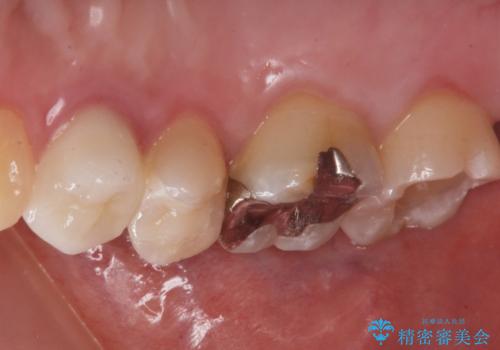

奥の歯に穴が空いている

- 奥の歯に穴が空いているとの事で来院。

拡大鏡下で虫歯を全て除去しゴールドインレーにて治療しました。